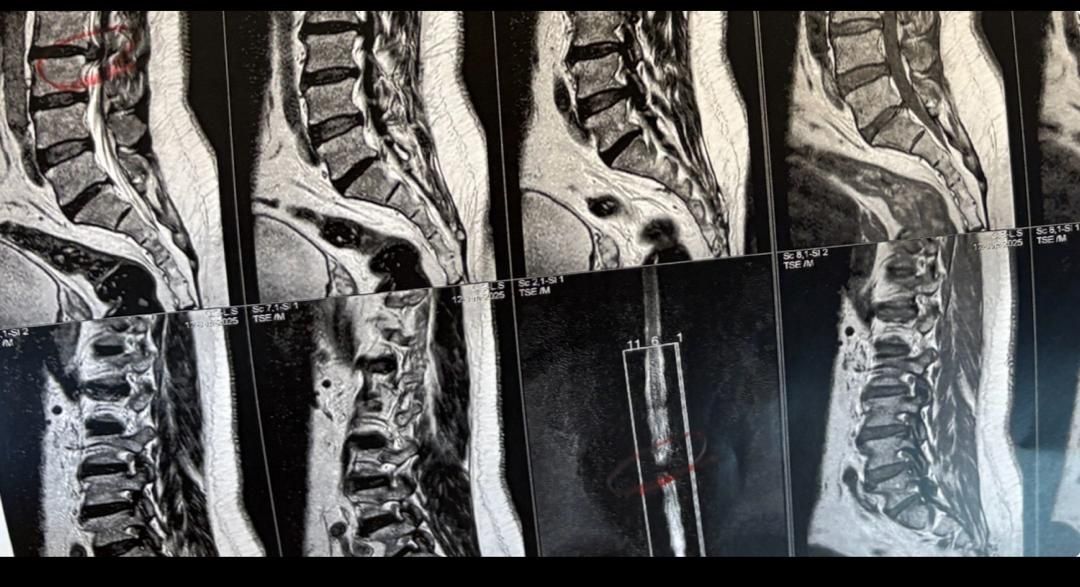

41 years old man presented to my clinic in October 2023 with acute and sever R neck pain with radicular pain to his R upper extremity along C6 dematom since 2 weeks ago. Examination didn’t show any upper motor signs. Was suggested urgent surgery

I ordered EMG/ NCV : showed mild R C6, C7 irritation without any active axonal loss

In his MRI was reported R. para R. IVF Massive extrusion. I decided to control his pain and manage this patient with reevaluation of patient every other session. For 5 sessions i just used acupuncture and laser and IFC and mild adjustments to his R. T3-T7 and mild arthosteem to above and below involved segment. Cervical adjustment considered contraindicated for this patient. From session 6th- 8th i started to use mild/gentle cervical decompression. He used soft cervical collar all the time. His pain decreased by 80 percent

I gave him cervical traction pump to be used 3-5 times per day at home for the next 3 months and i released the patient. He was evaluated every week once for one month and after that every 2 weeks. After 3 month I repeated MRI. Size of the herniated disc was reduced greater than 50 percent. Asked him to do another mri in 6 months

In general: Precise selection of the patients, examination,diagnosis, plan of management, reevaluation and treatment can be done by doctors of chiropractic for the patients with spinal disc herniation and stenosis Moreover giving reasonable time to these kind of patients under direct supervision by their chiropractic doctors can prevent unnecessary surgery. Proper selection of these kind of patients is another important fact that can be done precisely by chiropractors.

MRIs before and after proper management of this patient: